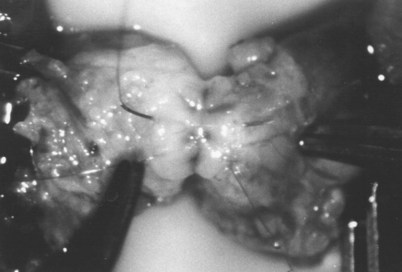

After opening the tunica vaginalis, the epididymis is inspected under the operating microscope. An anastomotic site is selected above the area of suspected obstruction, proximal to any visible sperm granulomas, where dilated epididymal tubules are clearly seen beneath the epididymal tunica (Fig. 22–29). A relatively avascular area is grasped with sharp jeweler’s forceps and the epididymal tunica tented upward. A 3- to 4-mm buttonhole is made in the tunica with microscissors to create a round opening that matches the outer diameter of the previously prepared vas deferens. The epididymal tubules are then gently dissected with a combination of sharp and blunt dissection until dilated loops of tubule are clearly exposed (Fig. 22–30). If the level of obstruction is not clearly delineated after the buttonhole opening is made in the tunic, a 70-µm diameter tapered needle from the 10-0 nylon microsuture is used to puncture the epididymal tubule beginning as distal as possible and fluid is sampled from the puncture site. When sperm are found, the puncture sites are sealed with microbipolar forceps, a new buttonhole is made in the epididymal tunic just proximally, and the tubule is prepared as described previously.

Figure 22–29 An anastomotic site is selected above the area of suspected obstruction, proximal to any visible sperm granulomas, where dilated epididymal tubules are clearly seen beneath the epididymal tunica, as marked by an arrow.

Figure 22–30 The epididymal tubules are then gently dissected with a combination of sharp and blunt dissection until dilated loops of tubule are clearly exposed.